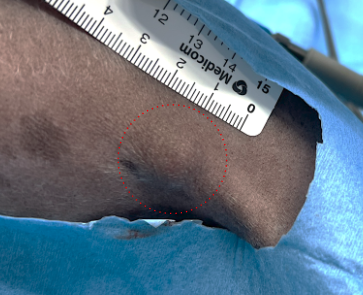

- 右膝窩部に直径1.1cmの軟性腫瘤を触知。

- 皮膚との固着を認めたが、底部(深部組織)との固着は認めなかった。

腫瘤辺縁より2cmの安全マージンを確保し、深部は筋膜2枚を含めて一括切除を行った。

同時に膝窩リンパ節の郭清を実施した。その結果、膝窩部に大きな皮膚欠損が生じた。